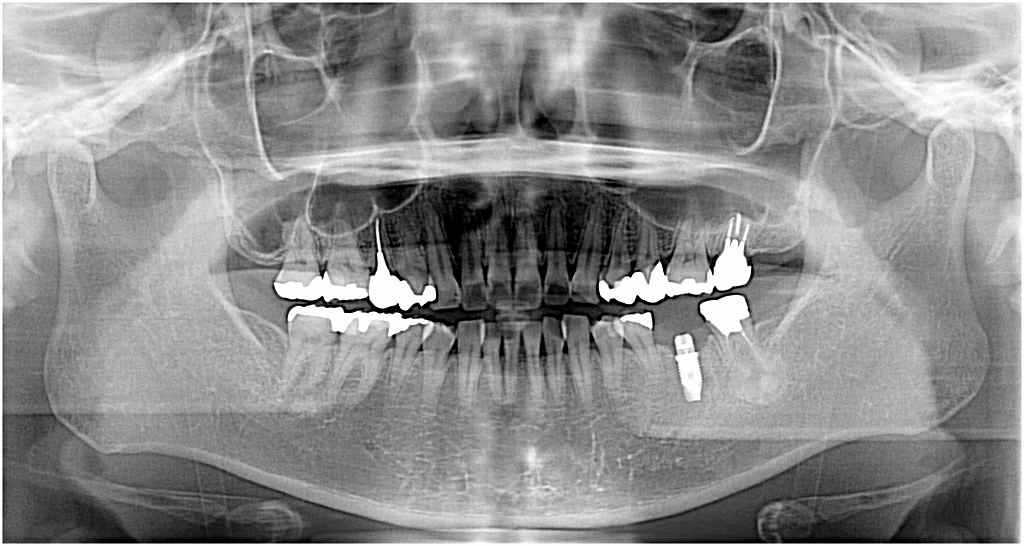

左下の奥歯のインプラント埋入|お知らせ |広島市安佐南区の歯科医院 左下の奥歯のインプラント埋入 トップ お知らせ・ブログ お知らせ 左下の奥歯のインプラント埋入 左下の奥歯のインプラント埋入 左下の6番ヘミセクション このクラウンが揺れてきました 骨吸収が認められます 割れているため抜歯となりました 抜歯しました 埋入していきました 補填材を入れ縫合して終了です このように埋入しています Web診療予約 初めての方へ 選ばれ続ける理由 院内設備について 歯が痛いしみる一般歯科 歯がぐらぐらする歯周病 健康な歯を保ちたい予防歯科 子供の虫歯予防をしたい小児歯科 銀歯をセラミックに審美歯科 白い歯を目指しませんか?ホワイトニング 矯正専門医がいるので安心矯正歯科 抜けた歯を補いたいインプラント・入れ歯 医院案内 スタッフ紹介 メリィハウス歯科クリニックオフィシャルホームページ ラベンダー歯科クリニックオフィシャルホームページ お知らせ・ブログ ホーム 診療科目 一般歯科 歯周病治療 予防治療 小児歯科 審美治療 ホワイトニング 矯正歯科 入れ歯・インプラント マウスピース矯正 初めての方へ 院長・スタッフ 設備紹介 医院案内・アクセス メニューを閉じる